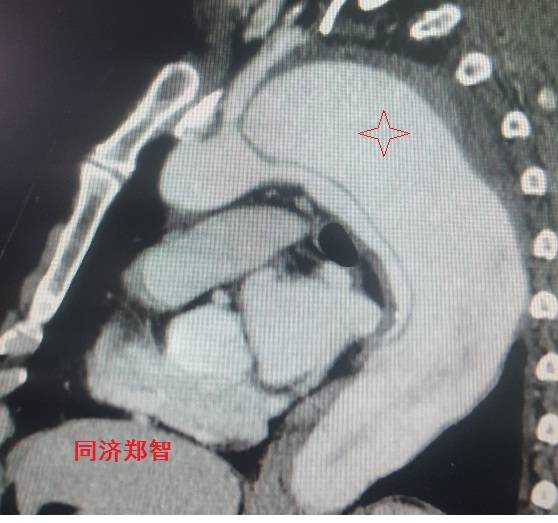

病例五

平扫CT提示主动脉弓层面及右肺动脉层面均可见主动脉血管腔内的内膜片影(红色箭头所示),CTA显示为A型主动脉夹层。